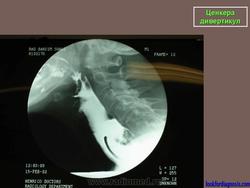

Ценкера дивертикул.

Barium swallow with fluoroscopy, lateral view</p> <p>During swallowing an outpouching of the posterior hypopharyngeal wall is clearly visualised at the level C5-C6, right above the upper oesophageal sphincter. The pouch is characterized by a narrow neck entrapping some barium after the swallowing.

ID: 12377 Zenker's diverticulum Dr Erik Ranschaert - 18 Nov 2010 Zenker's diverticulum

Дивертикул Ценкера.

67-летний мужчина